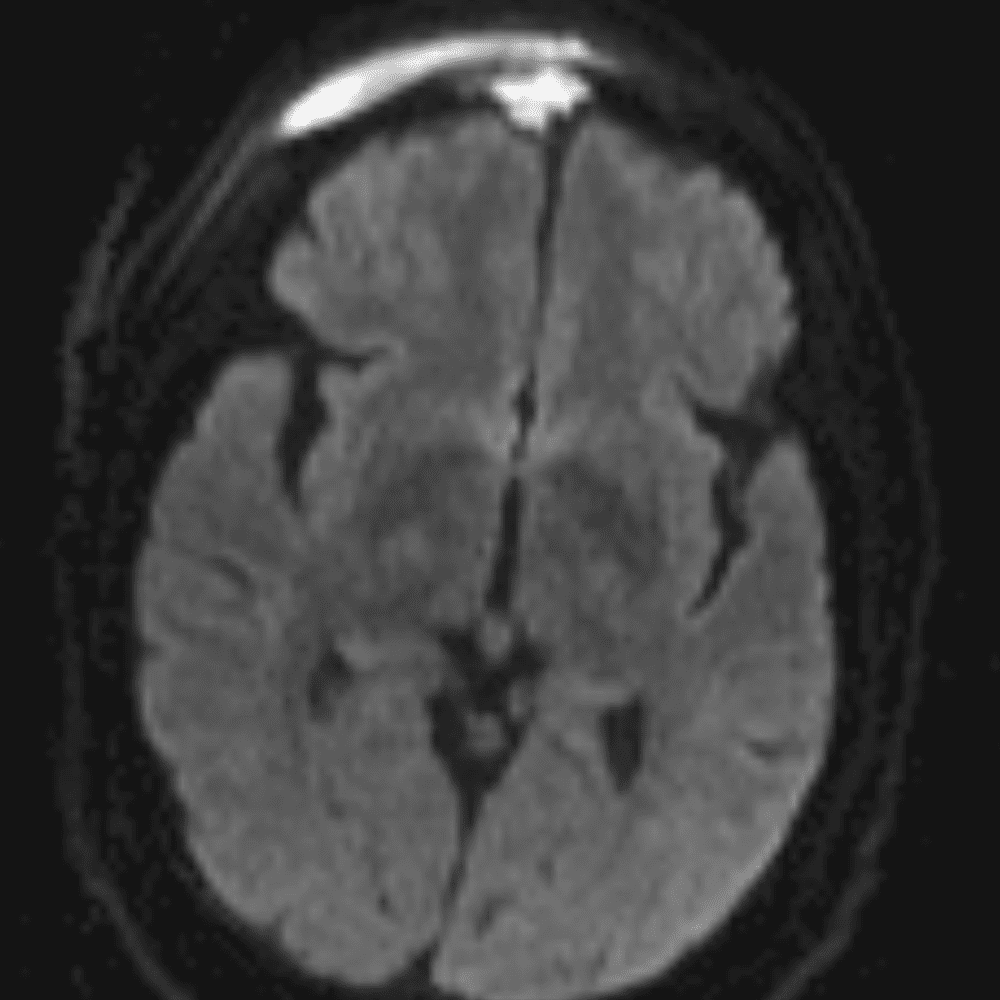

๋‹น์ง ์‹œ ํ”ํžˆ ๋ณผ ์ˆ˜ ์žˆ๋Š” ์‚ฌ๋ก€์˜ ์ „ํ˜•์ ์ธ ์˜ˆ๋ฅผ ํฌํ•จํ•ฉ๋‹ˆ๋‹ค.

39 ์‚ฌ๋ก€

์—ฐ์Šต

๋ฏธ๋ฌ˜ํ•˜๊ฑฐ๋‚˜ ์–ด๋ ค์šด ์‚ฌ๋ก€์™€ ์ผ๋ถ€ ์ •์ƒ ์‚ฌ๋ก€๋ฅผ ํฌํ•จํ•˜์—ฌ ๋‹น์ง์„ ์‹œ๋ฎฌ๋ ˆ์ด์…˜ํ•ฉ๋‹ˆ๋‹ค.

50 ์‚ฌ๋ก€